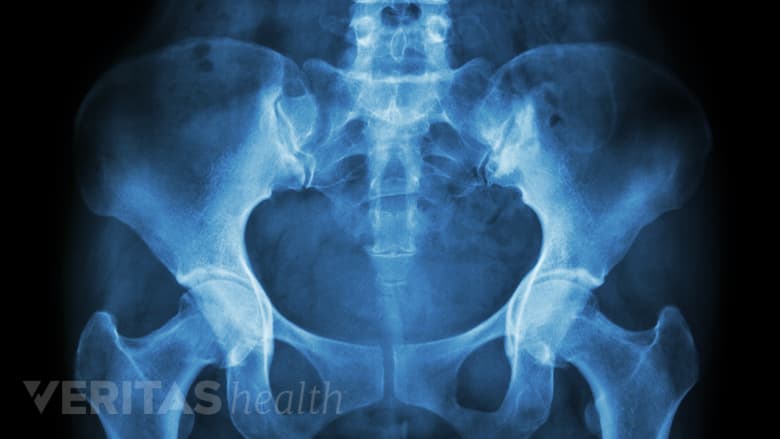

A wider pelvis in women makes them more susceptible to piriformis syndrome.

- Gender. Women are up to 6 times more likely to develop piriformis syndrome than men due to a wider pelvic bone.,